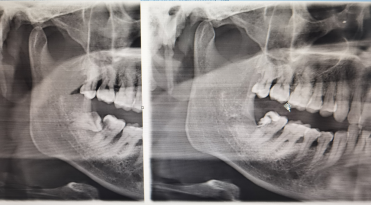

1.精准术前评估:通过CBCT三维影像技术清晰显示牙齿位置、牙根形态及与周围神经血管、上颌窦的关系,制定个性化拔牙方案规避手术风险。